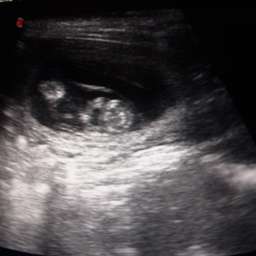

9.4.2015, 32.Tag: "Lieber Fiete! Ich habe gute Nachrichten für Dich: Du wirst Vater. Unser Date blieb nicht ohne Folgen.

5 kleine gesunde Wunder mit pochenden Herzen haben wir im Ultraschall gesehen. Freust Du Dich? Deine Adele"

Adeles Bauchumfang ist aktuell 45cm. Also 3cm Wachstum in 4 Tagen. Gewicht: 6,6Kilo. Oho, jetzt geht es los...!!!

Adeles Wunder

Adele hat den Ultraschall übrigens super gemeistert. Kahlrasur am Bauch hat sie abgelehnt. Aber ansonsten war sie ziemlich entspannt und in Vorfreude auf ihre Fleischwurst.